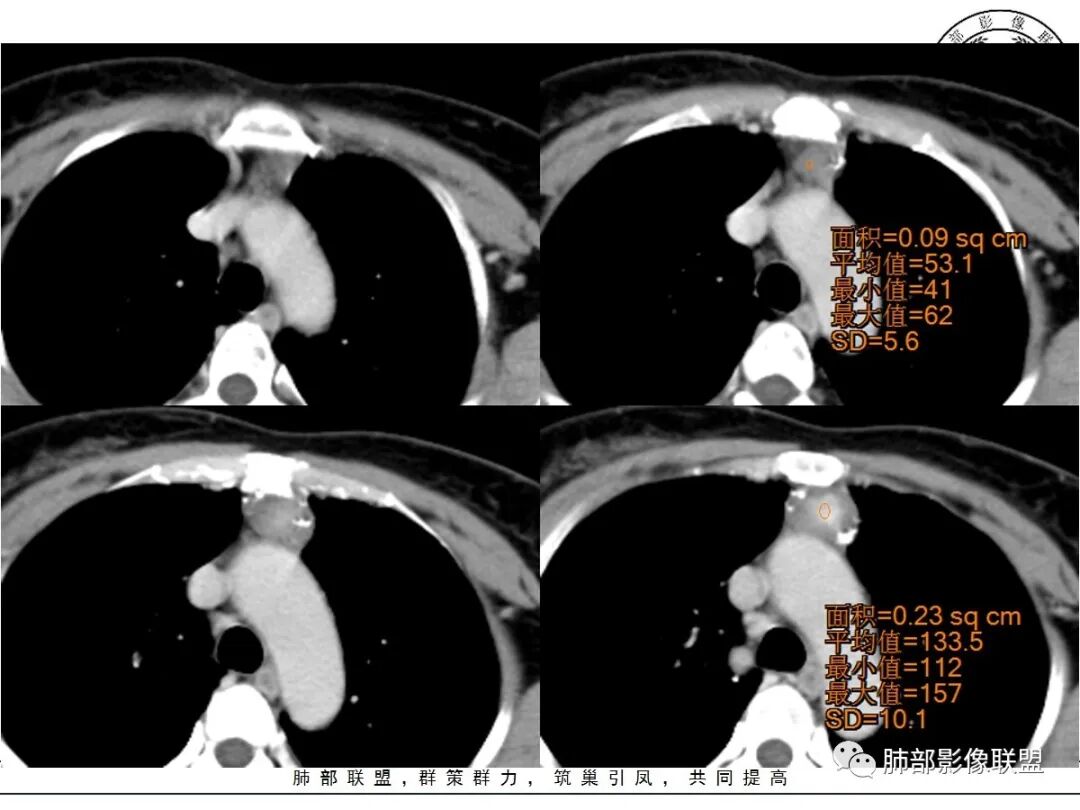

中央结节状强化, 类似于血管强化

前纵隔海绵状血管瘤的影像学特征包括:①发生于前纵隔的圆形、类圆形、不规则肿块影,边界清晰,与邻近结构分界清晰;②CT上呈稍低密度影,内见小结节状、小片状、针尖状的钙化灶,钙化灶、静脉石影是海绵状血管瘤的特征性表现。③增强后大多数肿块可显示肿块的范围及供血情况,动脉期病灶边缘呈点片状强化,静脉期及延迟期逐步向内填充,呈渐进性强化等典型特征,部分不强化或轻度强化,部分增强 后片状强化,强化程度与邻近血管相仿;血管瘤强化方式与肿块内组织成分、血窦内血栓、血流等因素有关;Moran等研究表明,肿块强化不均匀或呈轻度强化的原因可能与扩张的血窦腔内组织平滑肌增殖及炎性纤维化有关;肿块血管样强化可提示海绵状血管瘤。前纵隔海绵状血管瘤需与畸胎瘤、胸腺瘤、胸内甲腺肿、神经内分泌肿瘤等进行鉴 别 断:①畸胎瘤多呈混杂密度影,内有脂肪、毛发、钙化灶及水样密度;②胸腺瘤呈结节状、团块状影,密度较均匀,增强后强化较均匀,与周围组织分界清晰;③胸内甲状腺肿位于前上纵隔,平扫密度常较高,可见其上端与颈部甲状腺相连;④神经内分泌肿瘤多伴坏死囊变,点片状钙化,形态常呈分叶状或 不规则形,增强后肿瘤实性部分强化显著。

综上所述,海绵状血管瘤发生在纵隔非常罕见,且缺乏典型的临床症状及特异性影像, 应从肿块的位 置、大小、形态、与周围组织的 关 系 以及CT平扫、增强特点进行分析,如前纵隔肿块内有钙化灶、静脉石、增强后点片状血管样强化及渐进性强化等特点,应考虑纵隔海绵状血管瘤的可能;薄层CT及其多平面重组有利于发现细小钙化灶,而动态增强CT扫描能更好显示肿块内血管强化,有助于术前诊断与鉴别诊断。